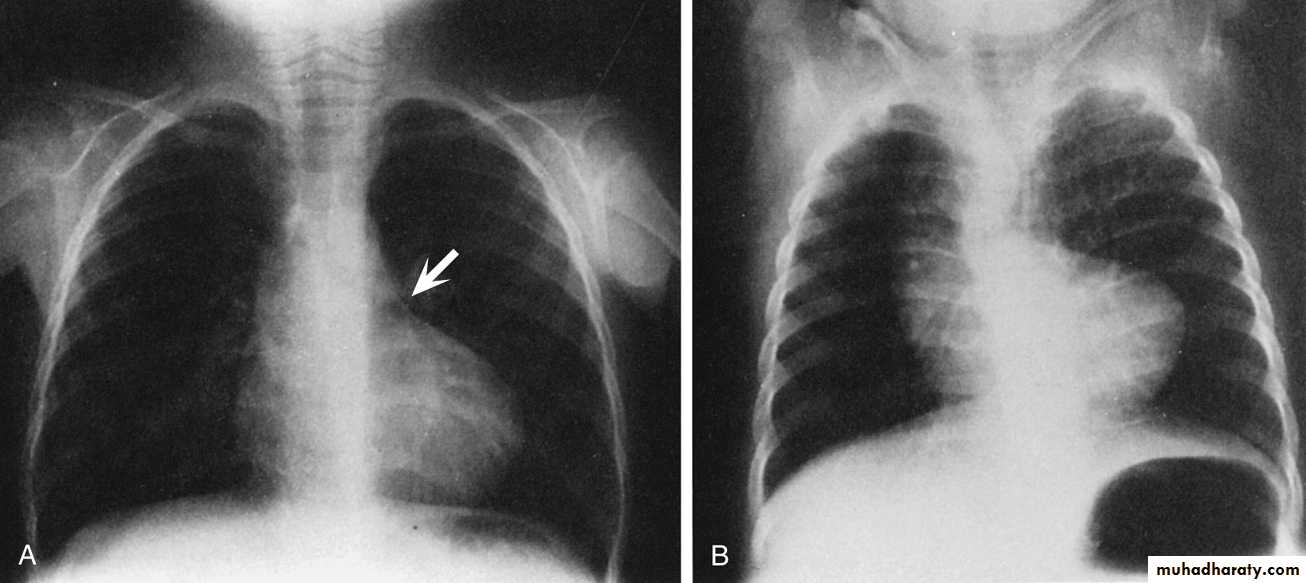

Chest X-Ray

Boot-shaped heart due to RVH + small pulmonary artery.

The lung fields usually appear oligemic

A right aortic arch occurs in approximately 25% of cases.

Chest film of TOF